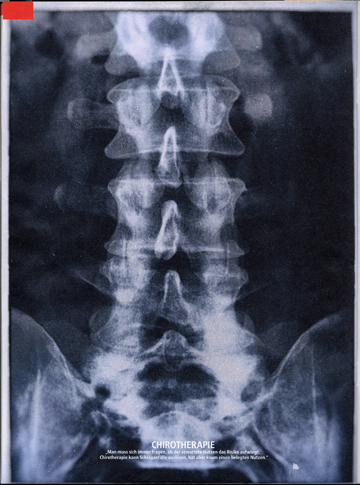

3. 4.Foto